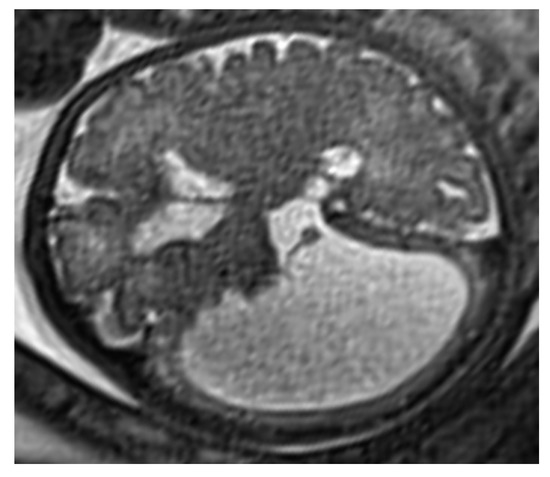

Holoprosencephaly